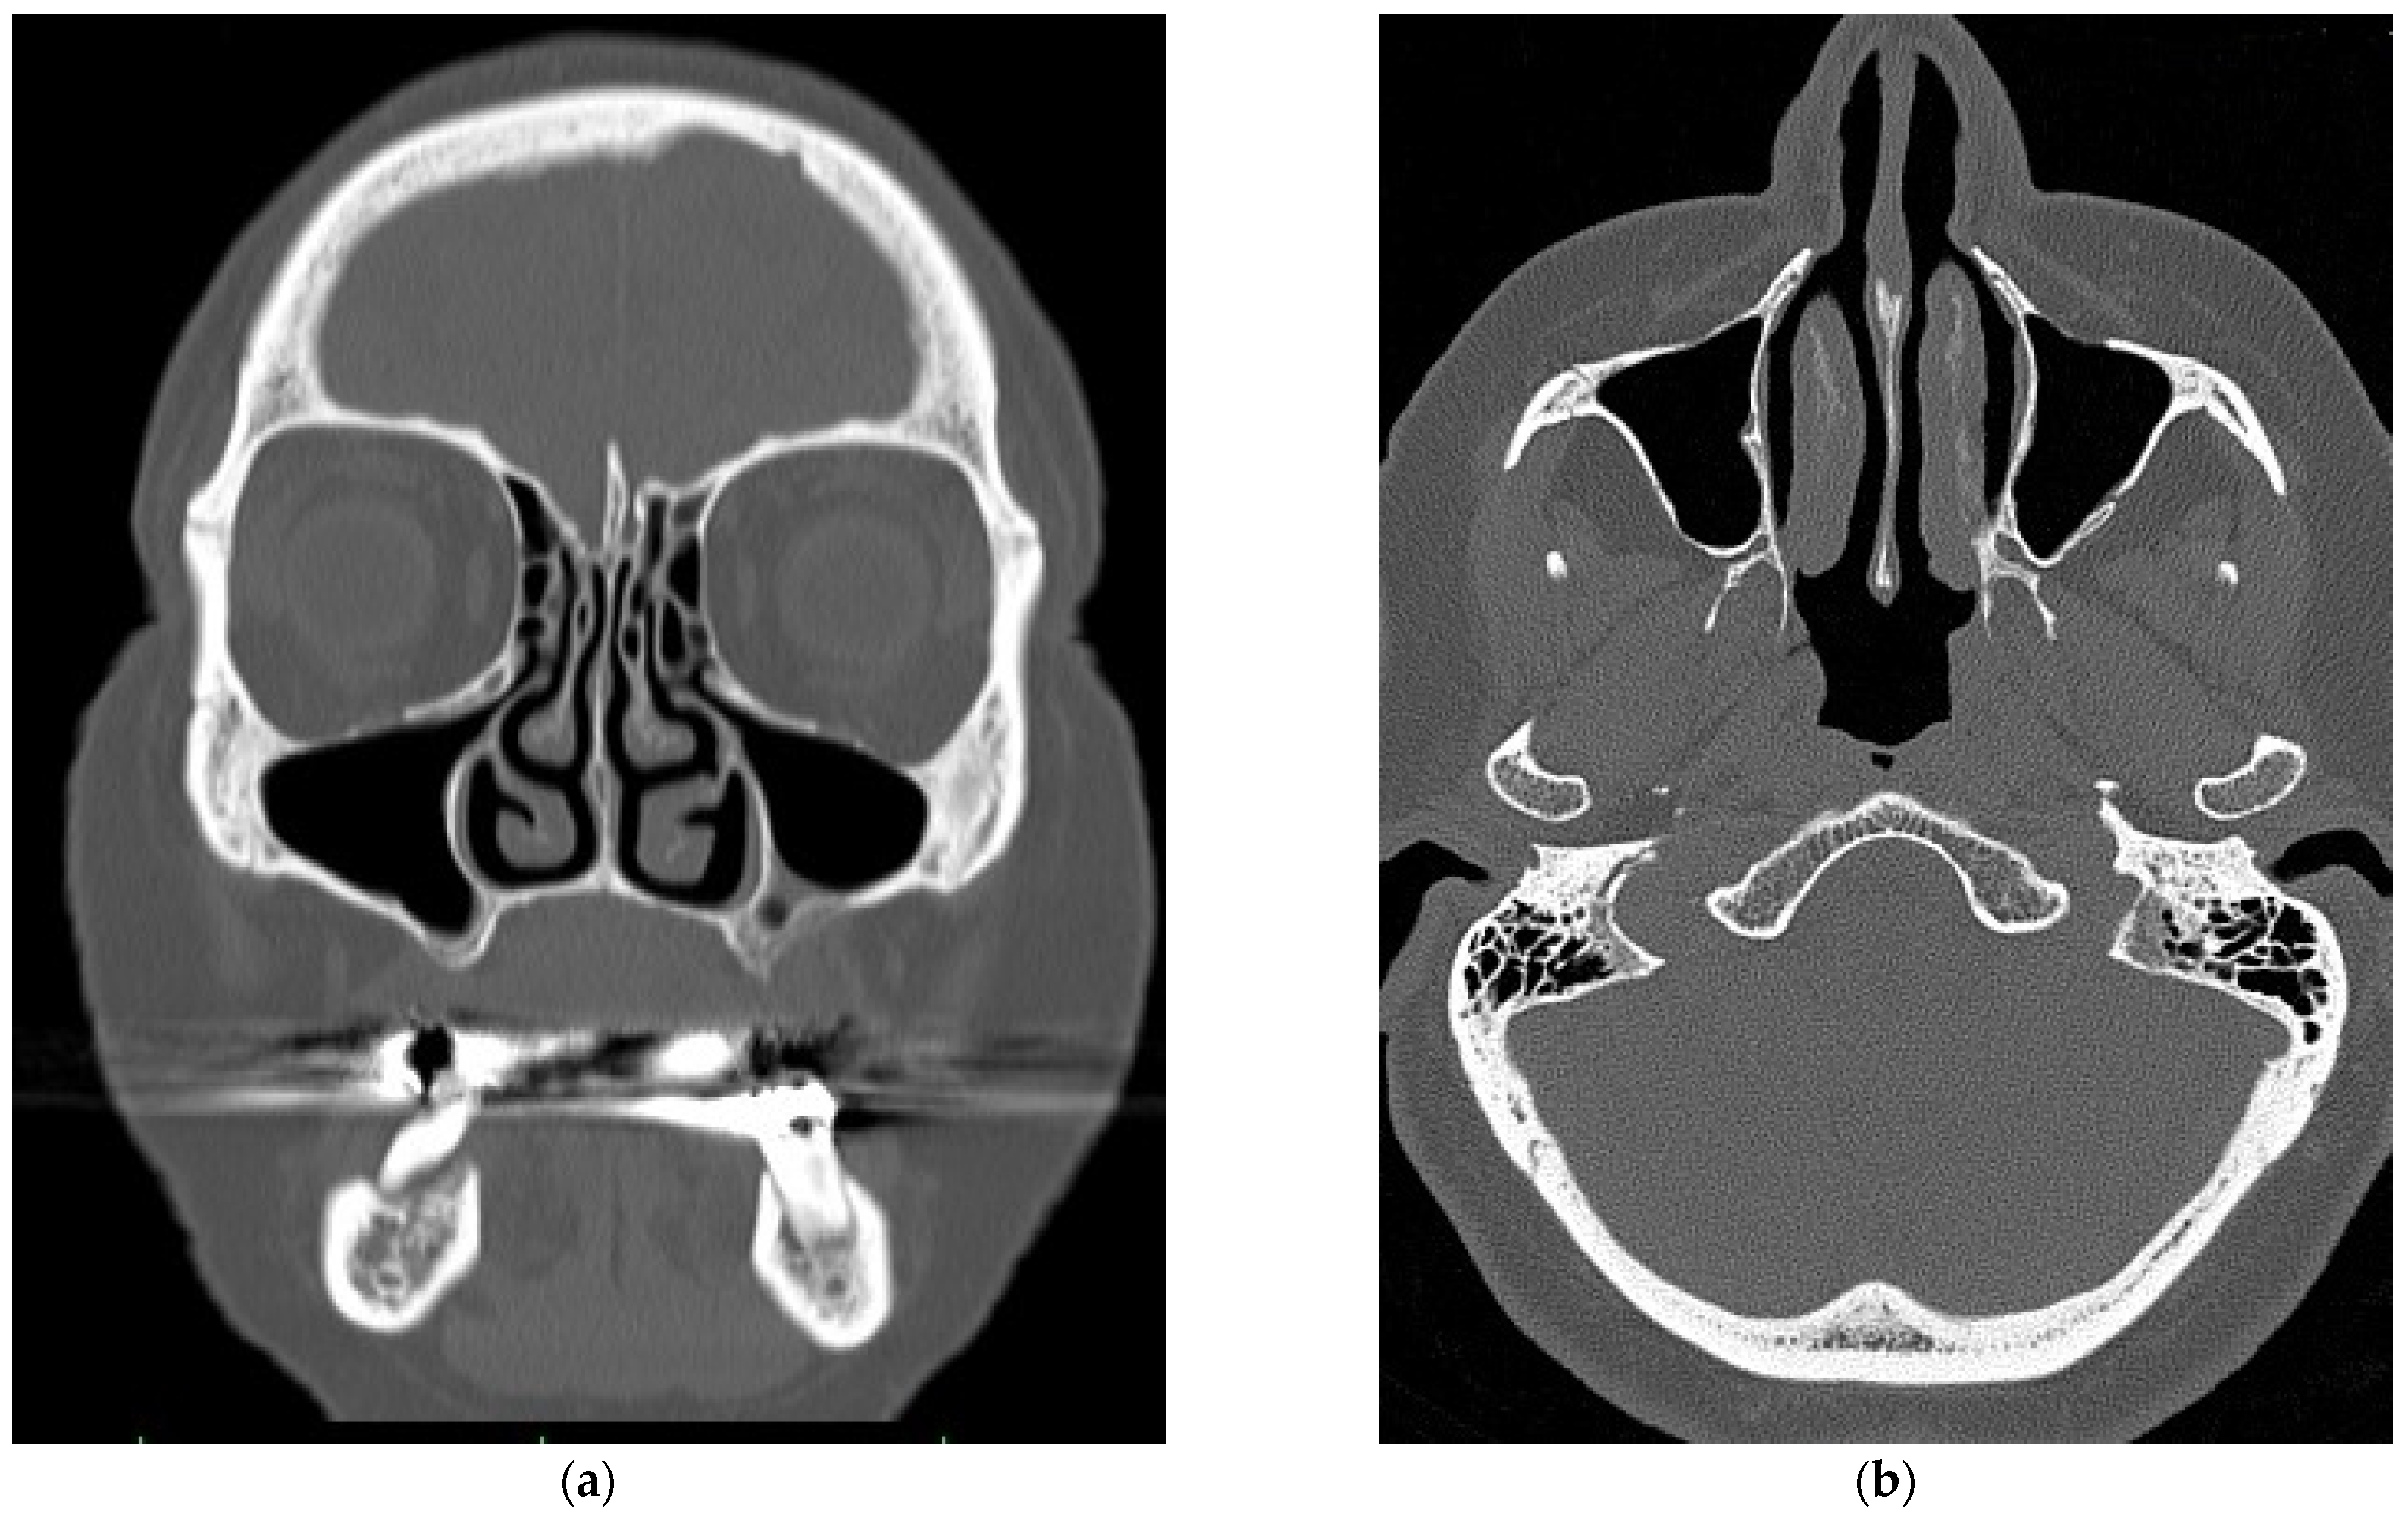

2.1. Virtual Model of the Nasal Cavity